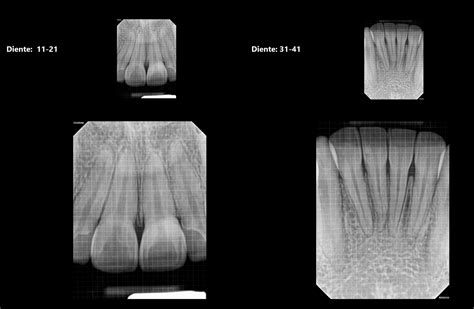

Una radiografía dental es una imagen que se obtiene usando rayos X para ver las estructuras internas de tu boca. Las radiografías son una herramienta esencial para examinar partes del diente y de la boca que no son perceptibles a simple vista y localizar posibles problemas, como las caries.

En el resultado, las caries suelen verse como áreas más oscuras del diente, debido a la menor densidad del tejido afectado por la desmineralización. La densidad de las estructuras que son atravesadas por los rayos X determina la apariencia de las mismas en la imagen radiográfica. De esta forma, podemos distinguir estructuras radiopacas y radiolúcidas.

Los dientes están formados por el esmalte, que es el tejido más denso del cuerpo humano con un 96-97% de sustancia mineral, dentina, cemento y complejo pulpar, compuesto este último por la cámara y los conductos radiculares que pueden ser considerados como el alojamiento vásculonervioso. Llama la atención la diferencia de densidades que existen en una estructura tan pequeña como es el diente, pudiendo considerarse el esmalte y la dentina como radiopacos y la cavidad pulpar como radiolúcida.

No cualquier tipo de radiografía es útil para diagnosticar las caries. Las radiografías idóneas para la detección de caries son las radiografías periapicales o las de "aleta de mordida". Son radiografías de pequeño tamaño y alta sensibilidad que nos muestran con gran detalle las coronas y raíces de los dientes. Existen diferentes tipos de radiografías que se utilizan para detectar caries:

- Radiografías periapicales: Permiten observar el diente completo, con las raíces y el hueso.